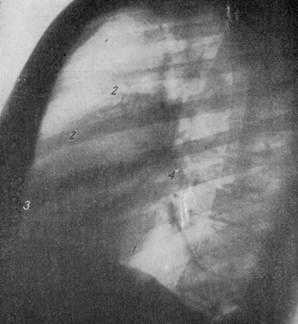

СХЕМА ПРОЕКЦИИ СЕРДЦА ВО ВТОРОМ КОСОМ ПОЛОЖЕНИИ (поворот левым плечом к экрану на 50—60°).

1 — контур левого желудочка; 2 — контур аорты; 3 — контур правого желудочка; 4 — контур правого предсердия; 5 — контур левого предсердия;

6 — трахея; 7 — бифуркация трахеи; 8 — ретрокардиальное пространство; 9 — ретростернальное пространство; 10 — левый бронх.

РЕНТГЕНОГРАММА НОРМАЛЬНОЙ ГРУДНОЙ КЛЕТКИ ВО ВТОРОМ КОСОМ ПОЛОЖЕНИИ.

1 — дуга левого желудочка; 2— восходящая часть аорты; 3 — дуга правого желудочка; 4 — дуга правого предсердия; 5 — дуга левого предсердия.